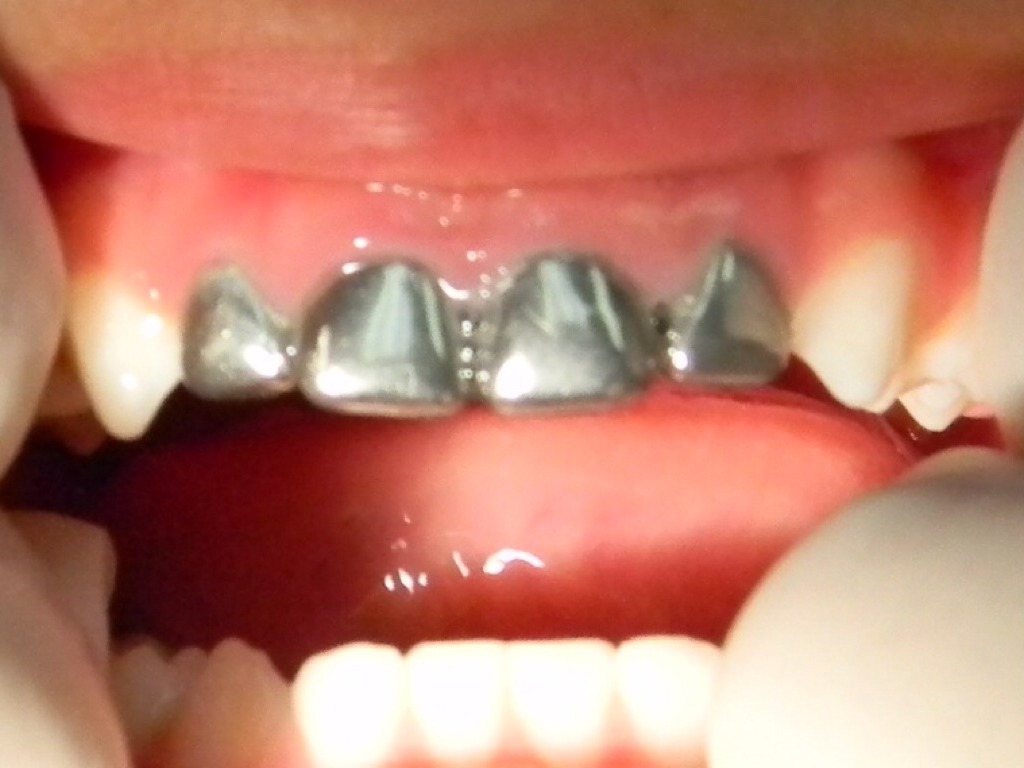

CORONAS

Untitled Slide

29.